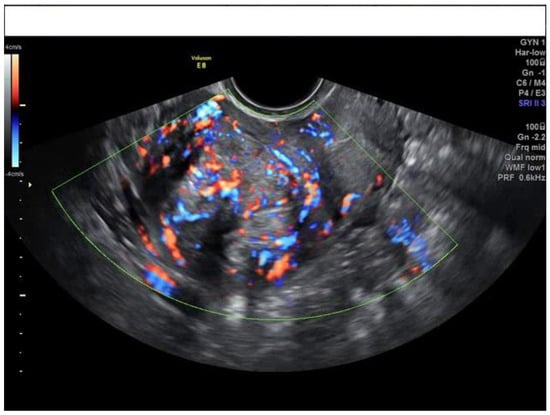

| Ultrasound Feature | Frequency in Uterine Sarcomas |

|---|---|

| Irregular contour | 52.8% |

| No visible myometrium | 24.6% |

| Not uniform cchogenicity | 77.4% |

| Irregular cystic areas | 44.6% |

| Intralesional color score 3–4 | 67.9% |